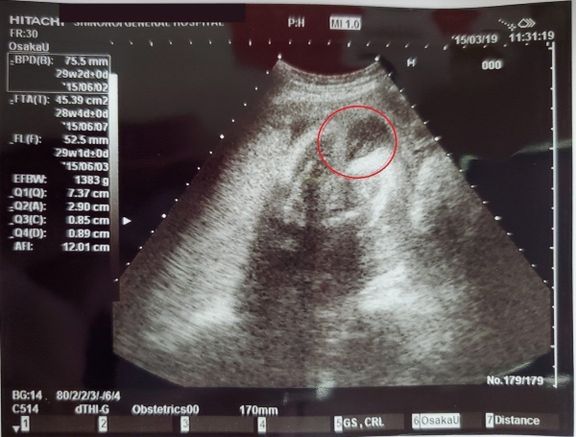

EFBW(胎児推定体重)=1383g -